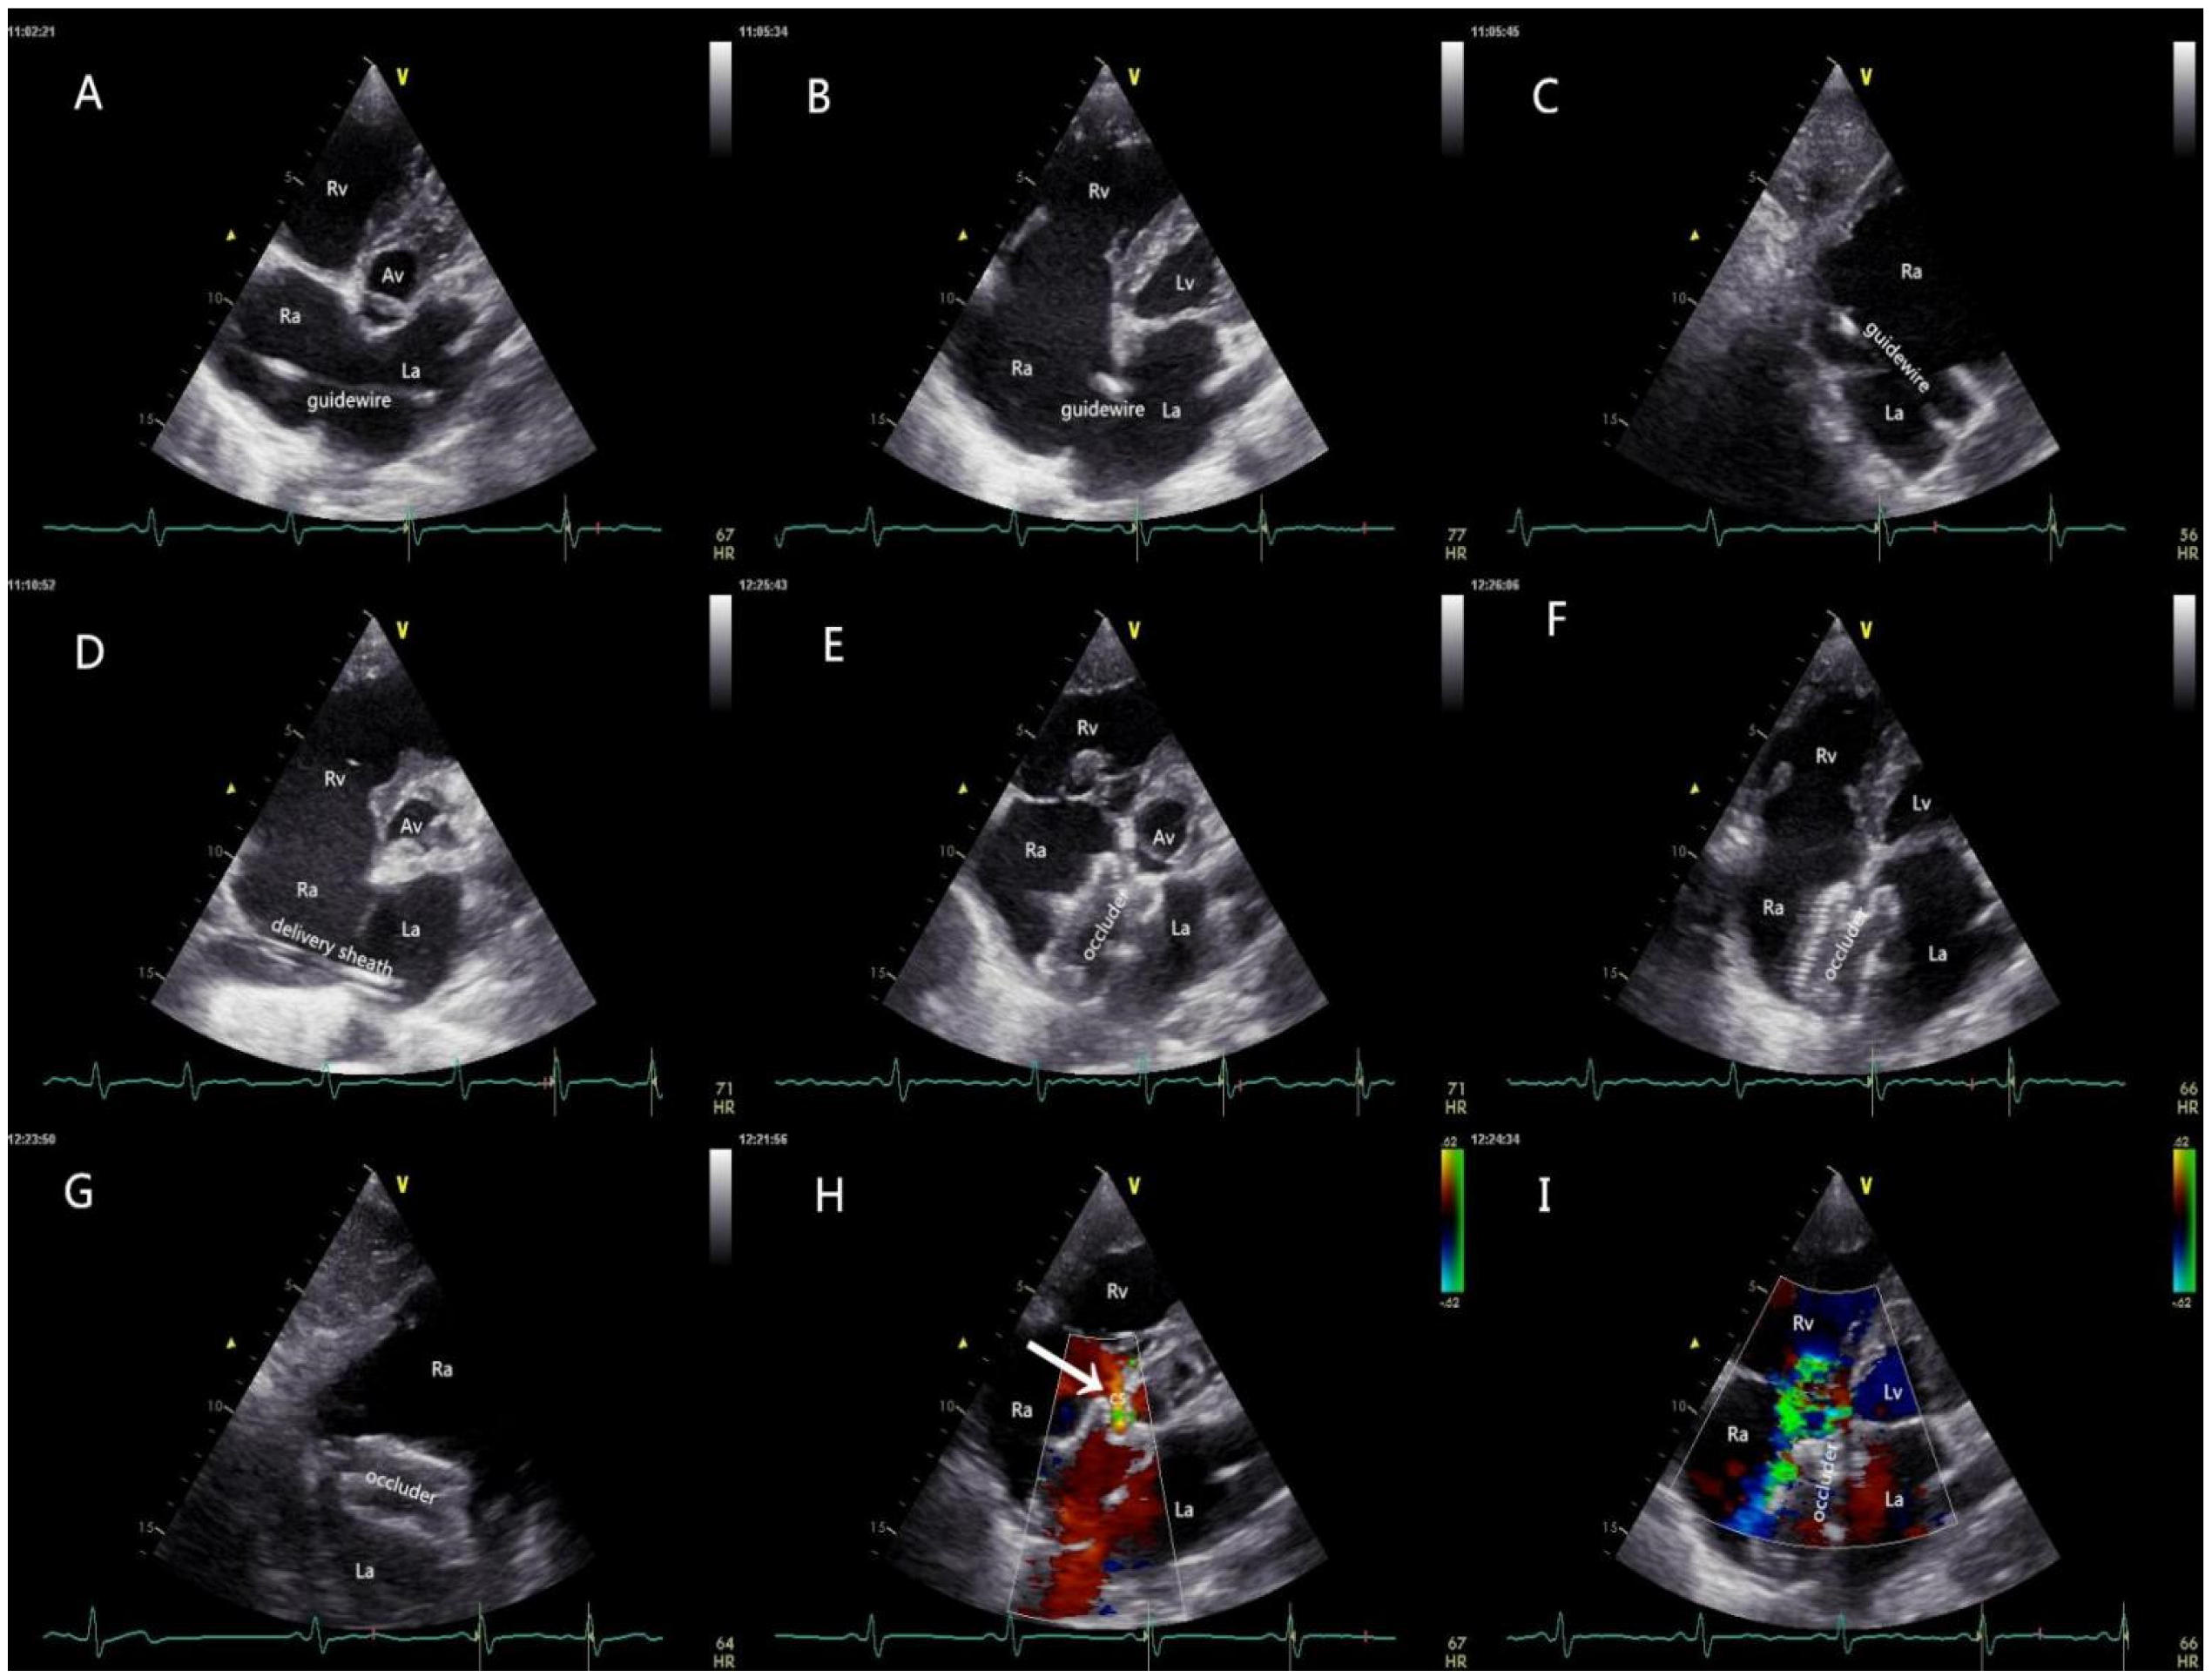

Patients with an adequate thoracic ultrasonic window received local anesthesia and underwent TTE-guided PAC, and the remainder received the procedure under traditional TEE guidance and general anesthesia. Right heart and peripheral artery catheterization were routinely performed to achieve perioperative hemodynamic monitoring. The patient was then placed in a 30-degree right-chest elevated position. The size of the Amplatzer Septal Occluder (LZASD, SHANGDONG VISEE MEDICAL DEVICES Co., Ltd., China) was completely based on the result of echocardiography (oversized by 4 mm to 6 mm more than the maximum dimension of the defect) rather than balloon sizing in all patients. The procedure is demonstrated in Figure 3. The patients receiving regional anesthesia were sent directly to the general ward, and those who underwent general anesthesia were sent to the ICU. Anticoagulation via the oral administration of dipyridamole or aspirin was carried out for 3 months after the procedure.

Figure 3.

Procedural protocol. (A) The guidewire was inserted from the RA into the LA via the femoral vein under the guidance of TTE; (B,C) the tail end of the high-echo guidewire was confirmed to be inside the LA in the four-chamber view and the short-axis subcostal view; (D) a delivery sheath was inserted along the guide-wire into the LA, and then the inner core and the guidewire were withdrawn; (E) the occluder was delivered carefully through the sheath under the real-time guidance of TTE, and the LA disc was opened; (F,G) the occluder was completely released, and the two discs of the occluder were accurately parallel to the plane of the atrium septal; (H) the blood flow from CS was fluent (white arrow); (I) the shunt between RA and LA disappeared, and no mitral regurgitation was detected with TTE. Mild tricuspid regurgitation still existed, as confirmed before the interventional catheterization. TTE: transthoracic echocardiography; RA: right atrium; LA: left atrium; RV: right ventricle; LV: left ventricle; TV: tricuspid valve; AV: aortic valve; CS: coronary sinus.